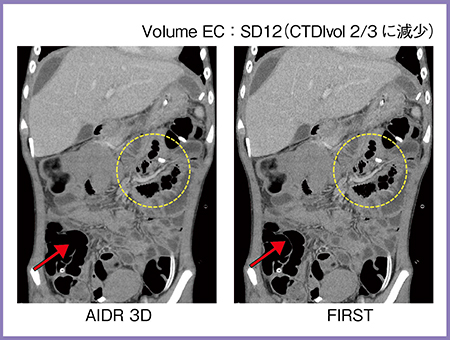

最新の逐次近似画像再構成法FIRSTによる小児CT画像を紹介する。

症例5は,11歳,虫垂炎の症例で,広範な腹膜炎を併発し,複数箇所に膿瘍を形成している(図6)。膿瘍ドレナージ術後の再評価において,条件を下げてXYZ方向で管電流を変調させるVolume EC撮影を行った。通常SD10の設定をSD12とし,CTDIvolを2/3に低減して撮影した。AIDR 3DとFIRSTを比較すると,同じ撮影条件でありながら,FIRSTでは腸管と腸管の間の薄い壁が描出されており(→),血管構造の辺縁も明瞭に描出され(○)画質が向上している。腸管の動きによると思われるドレナージチューブ周辺のアーチファクトも軽減されており,大いに期待が持てる技術である。

図6 症例5:虫垂炎,汎発性腹膜炎術後,遺残膿瘍ドレナージ術後(11歳)